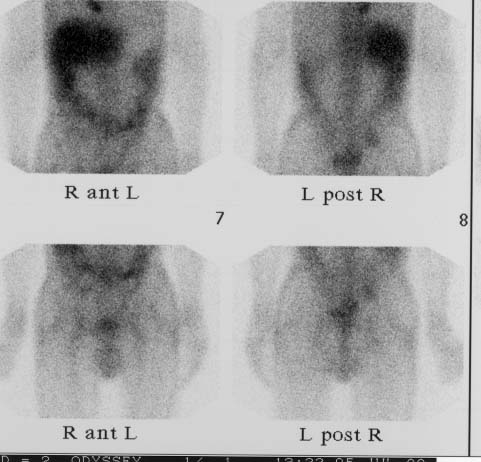

CaseYW01

- Age/Sex: 50M

- Chief Complaint: 頭痛,発汗過多,動悸,体重減少

- Clinical

Course: アルコール性肝炎にて経過観察中。最近1年間、高血圧症の診断で降圧薬を内服している。

- Lab. Data: 末梢血中濃度 Epinephrine 43 pg/ml (基準値 0-80),

Norepinephrine 31400 pg/ml (基準値 90-420), Dopamine 122 pg/ml

(基準値 0-30)

- Images:

- X-CT

- 131I MIBG,

48h

123I

MIBG, 24h

123I

MIBG, 24h

あなたの診断は What

is your first impression?

123I

MIBG, 24h

123I

MIBG, 24h